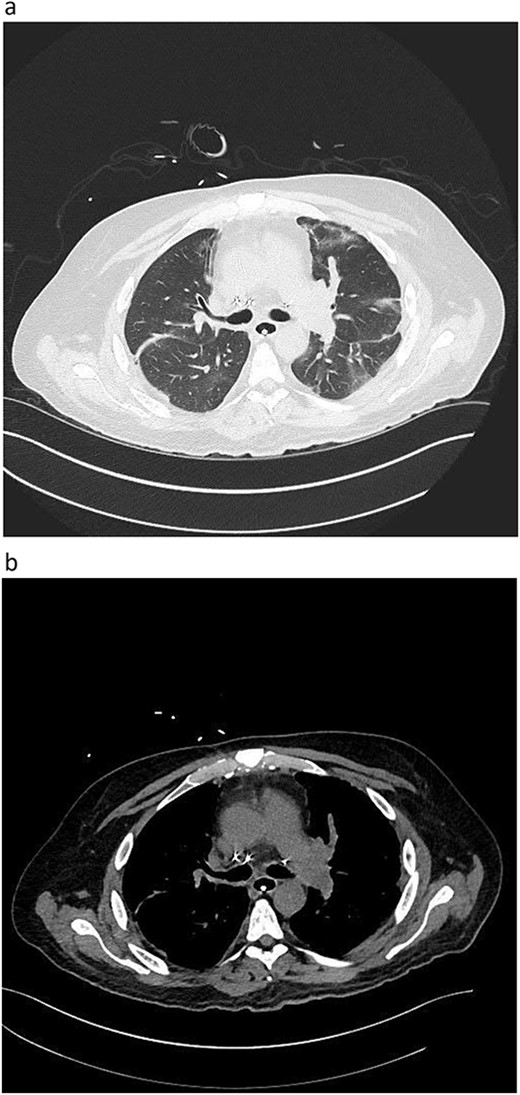

A woman in her mid-30s had hypoxic brain injury after cardiac arrest from drug overdose and was declared brain dead 4 days after hospitalization. PaO2 was 466 mm Hg with a fraction of inspired oxygen of 1.0 and positive end-expiratory pressure of 5 cm H2O. Chest computed tomography (CT) angiography showed a subtle filling defect in the left pulmonary artery (LPA) (Fig. 1). Intraoperative bronchoscopic findings were unremarkable. On visual inspection, the lungs appeared normal and had adequate compliance. We accepted and procured the lungs en bloc. Retrograde flushing evacuated several small clots from the pulmonary arteries. Both lungs were packed and transported as usual.

Donor angio CT scan: (a) filling in the left PA, (b) reduction of blood supply of the left lung.